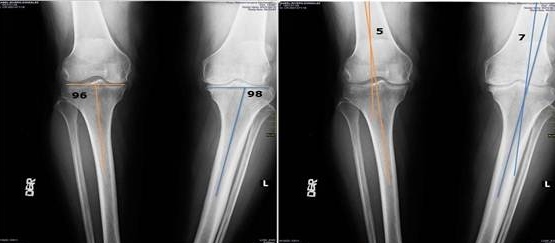

La Artroscopia permite tratar lesiones articulares mediante pequeñas incisiones, reduciendo el tiempo de recuperación y las complicaciones. Este procedimiento se aplica principalmente en rodillas, hombros y otras articulaciones, con resultados efectivos y seguros.